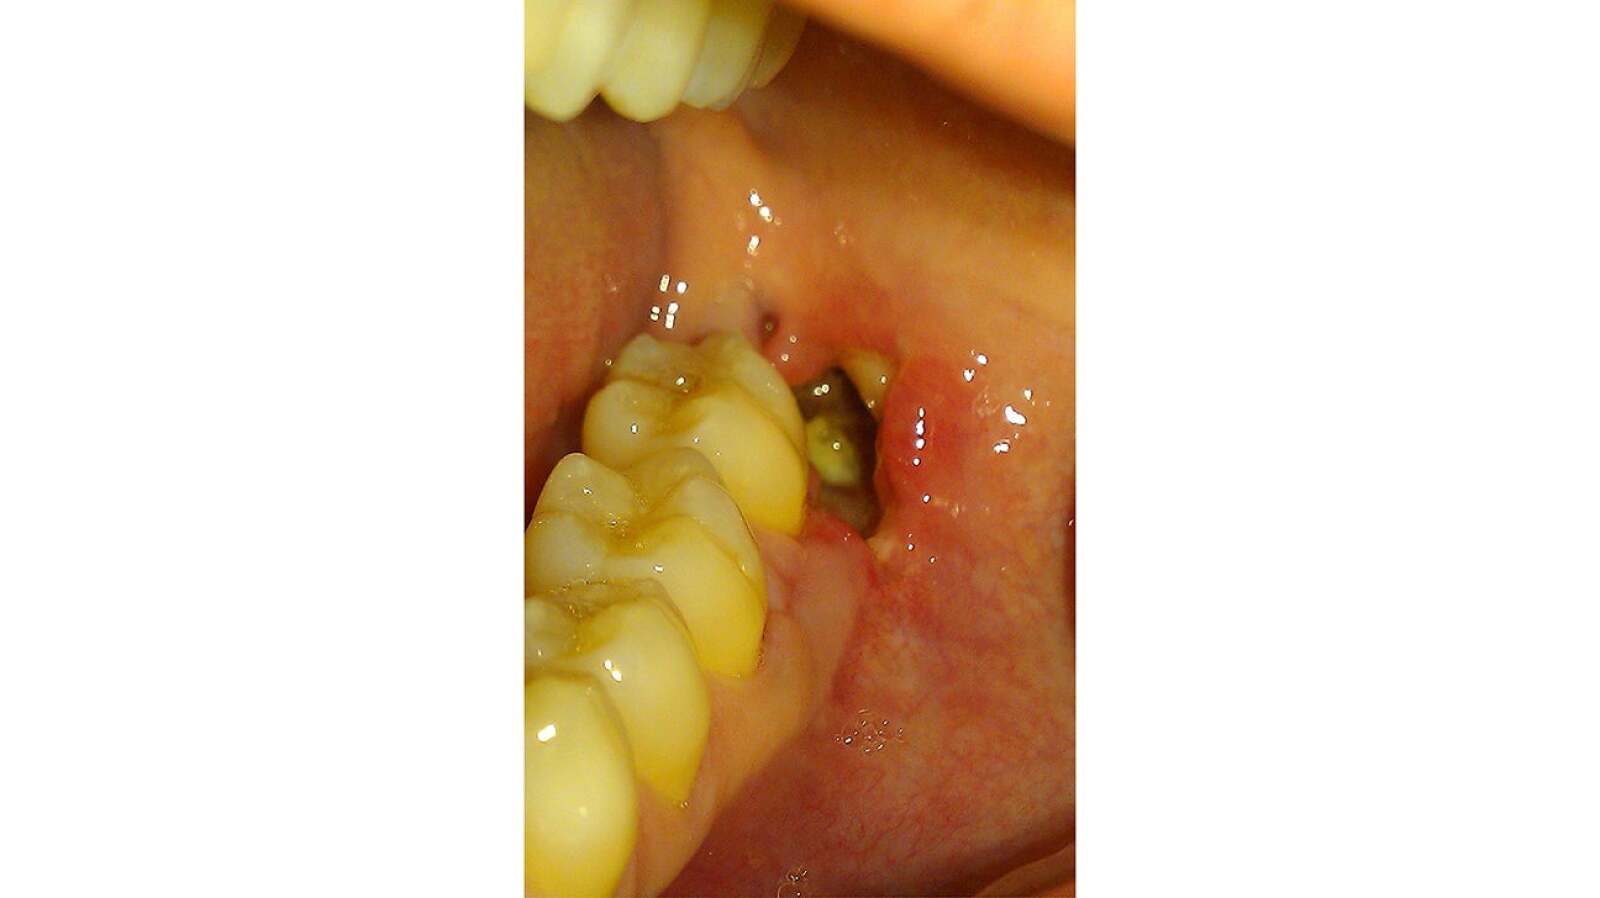

From www.ncbi.nlm.nih.gov

[Figure, Alveolar osteitis (dry socket).] StatPearls NCBI Bookshelf Does Dry Socket Bleed A Lot A user shares their experience and tips on how to prevent dry socket after having four impacted wisdom teeth extracted. Dry socket is a painful complication that occurs when the blood clot in the socket is removed or never forms. Dry socket is a painful condition when a blood clot falls out of the extraction site too early. The socket. Does Dry Socket Bleed A Lot.